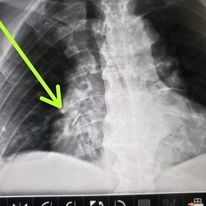

Puedo hacer una interpretación profesional de estudios de imágen cómo radiografías de tórax, ultrasonidos de tórax, tomografía de tórax en sus modalidades de tomografía simple, contrastada, angiotomografia, tomografía simple de alta resolución (T.A.C.A.R)